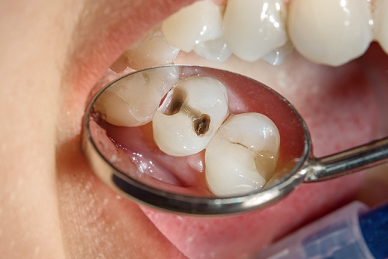

General Dentistry

General Dentistry at Neua Dental - Preventive and Restorative Care Services in Singapore

Discover the Importance of General Dentistry for Your Oral Health

General dentistry involves the prevention, diagnosis, and management of common dental conditions. It includes services such as routine dental examinations, scaling and polishing, fillings, and care for the gums.

Regular visits to a general dentist support the early detection and management of common dental issues such as tooth decay and gum disease. Maintaining good oral hygiene is an important part of overall health. Some studies have observed associations between oral health and systemic conditions such as diabetes and cardiovascular disease.

tooth cavity image